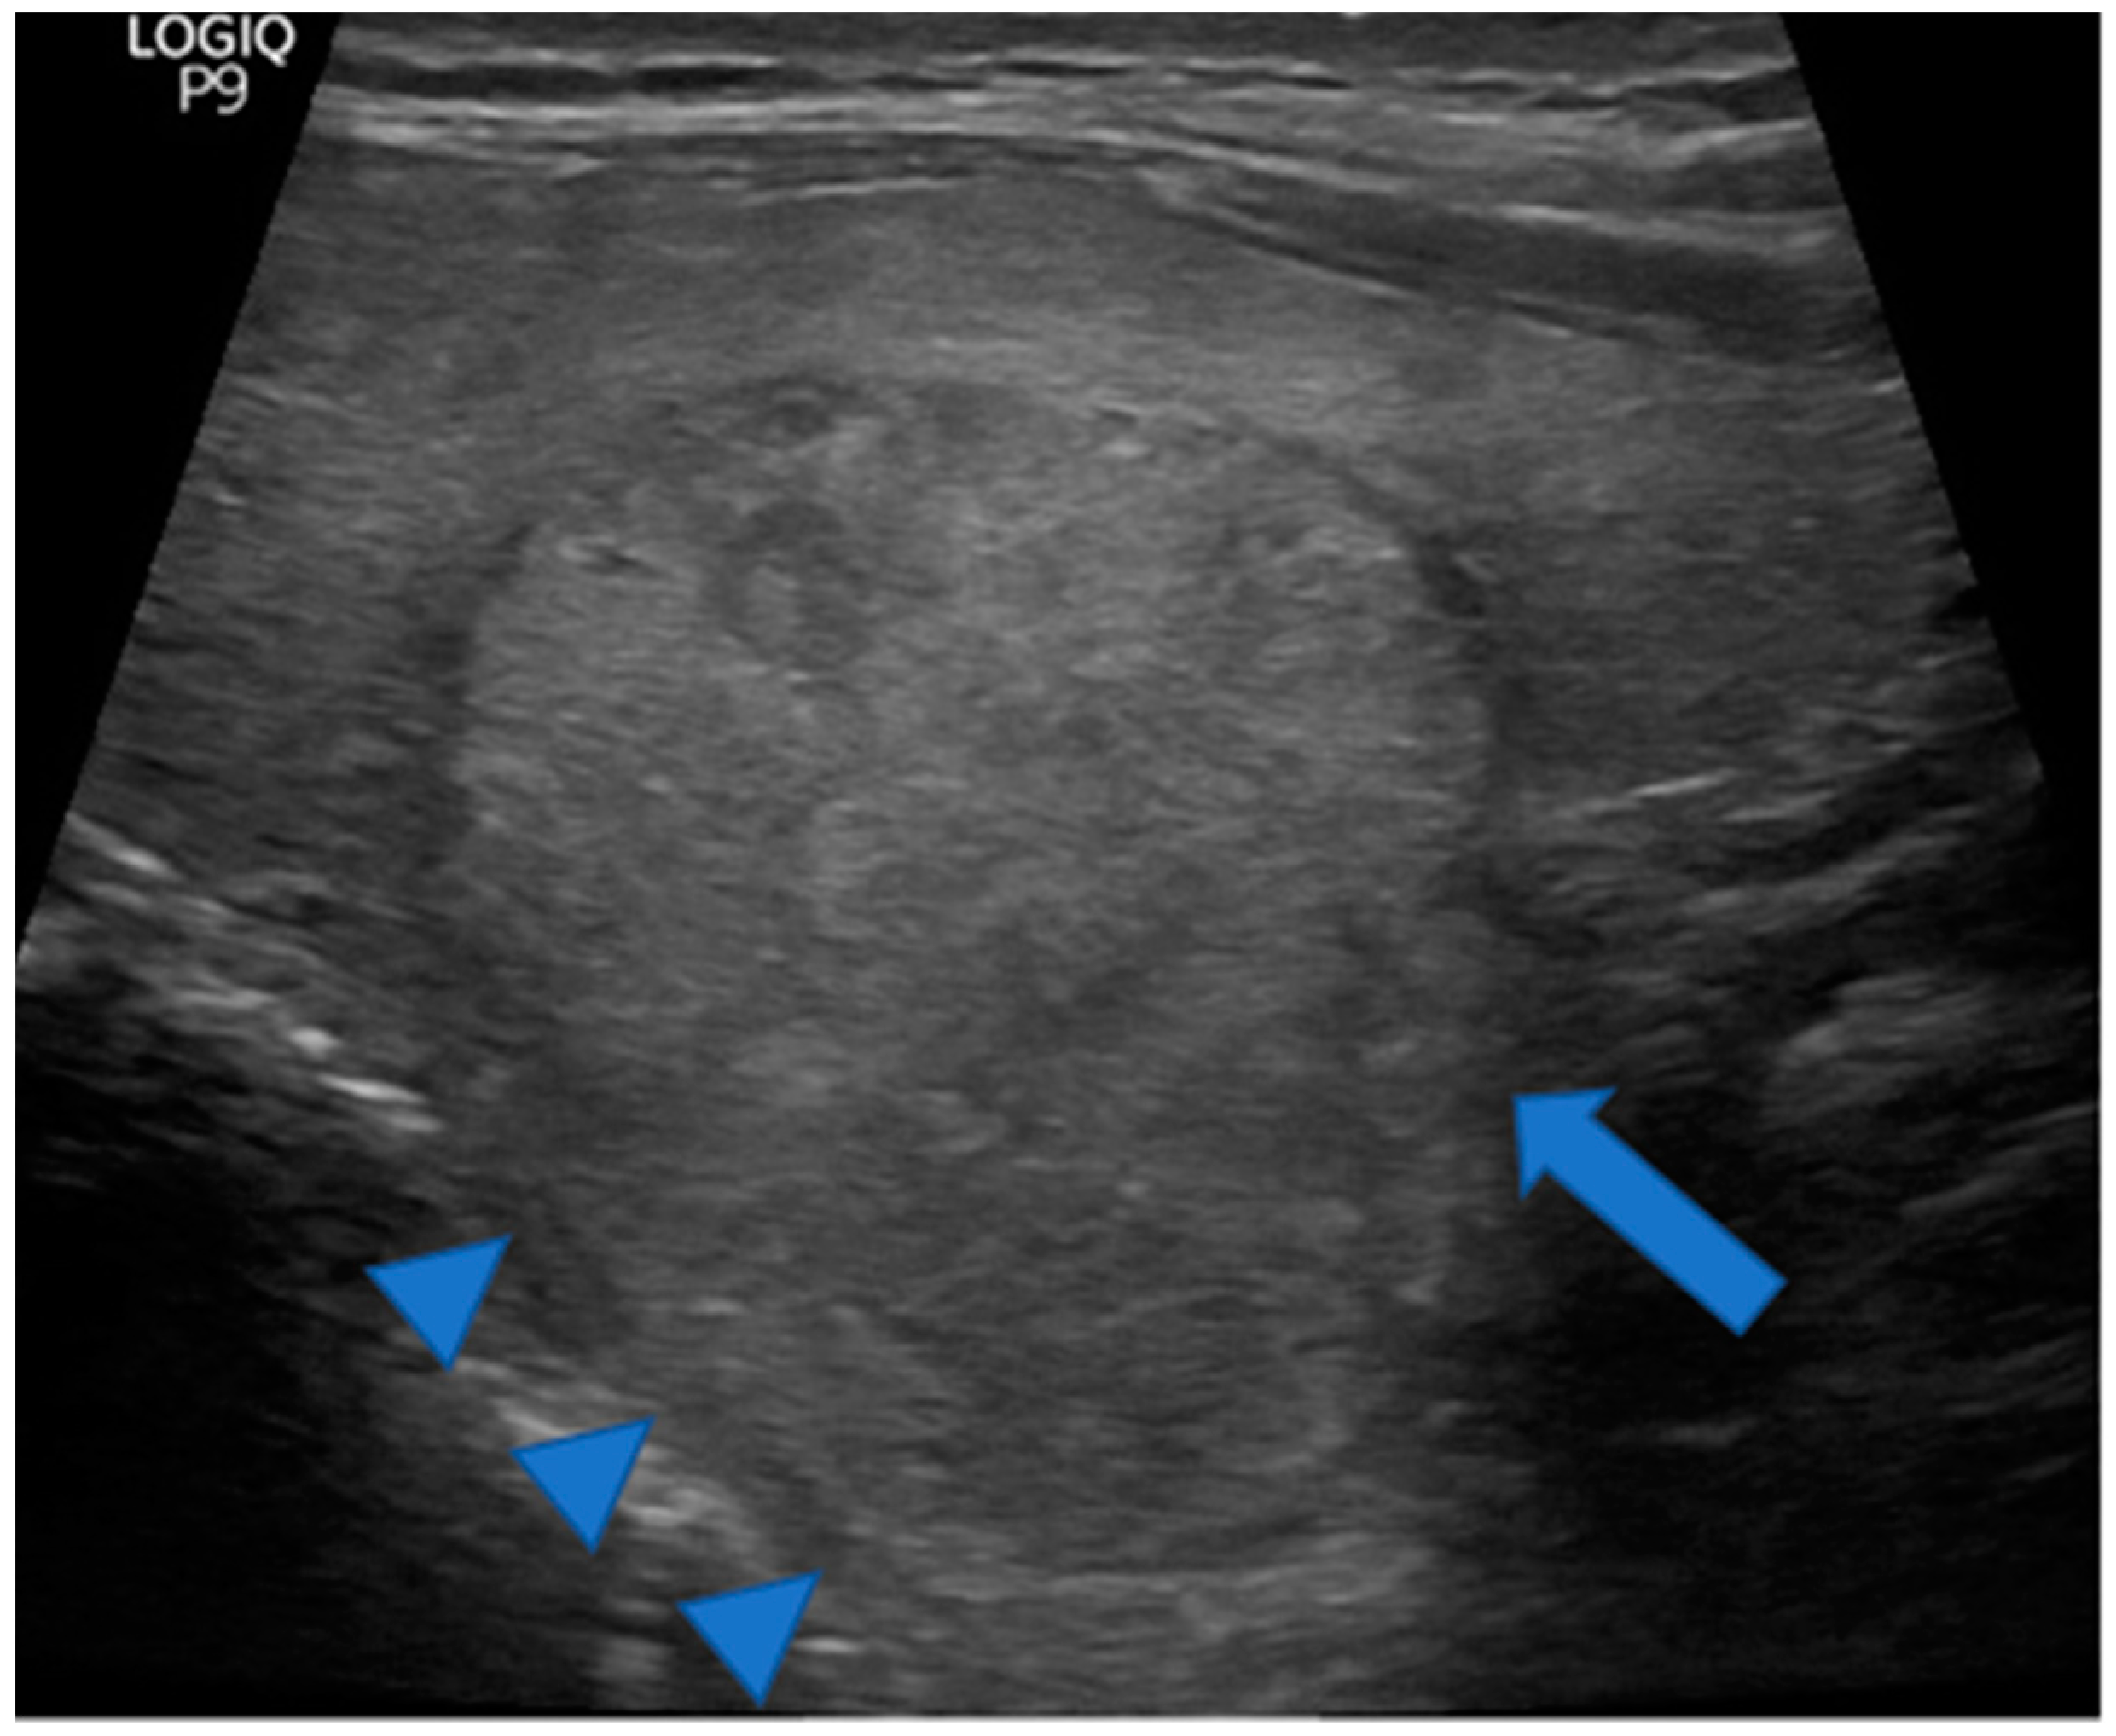

Figure 5.

Huge TTW nodule extending into a prominent posterior horn (arrowheads). Note the thyroid parenchyma extending along the cranial portion of the nodule (arrowheads) but not along the caudal portion (arrow) arguing for a pre-existing posterior horn. A pre-existing posterior horn may have channeled the way for nodule growth causing its taller than wide shape. The nodule was benign at cytology.